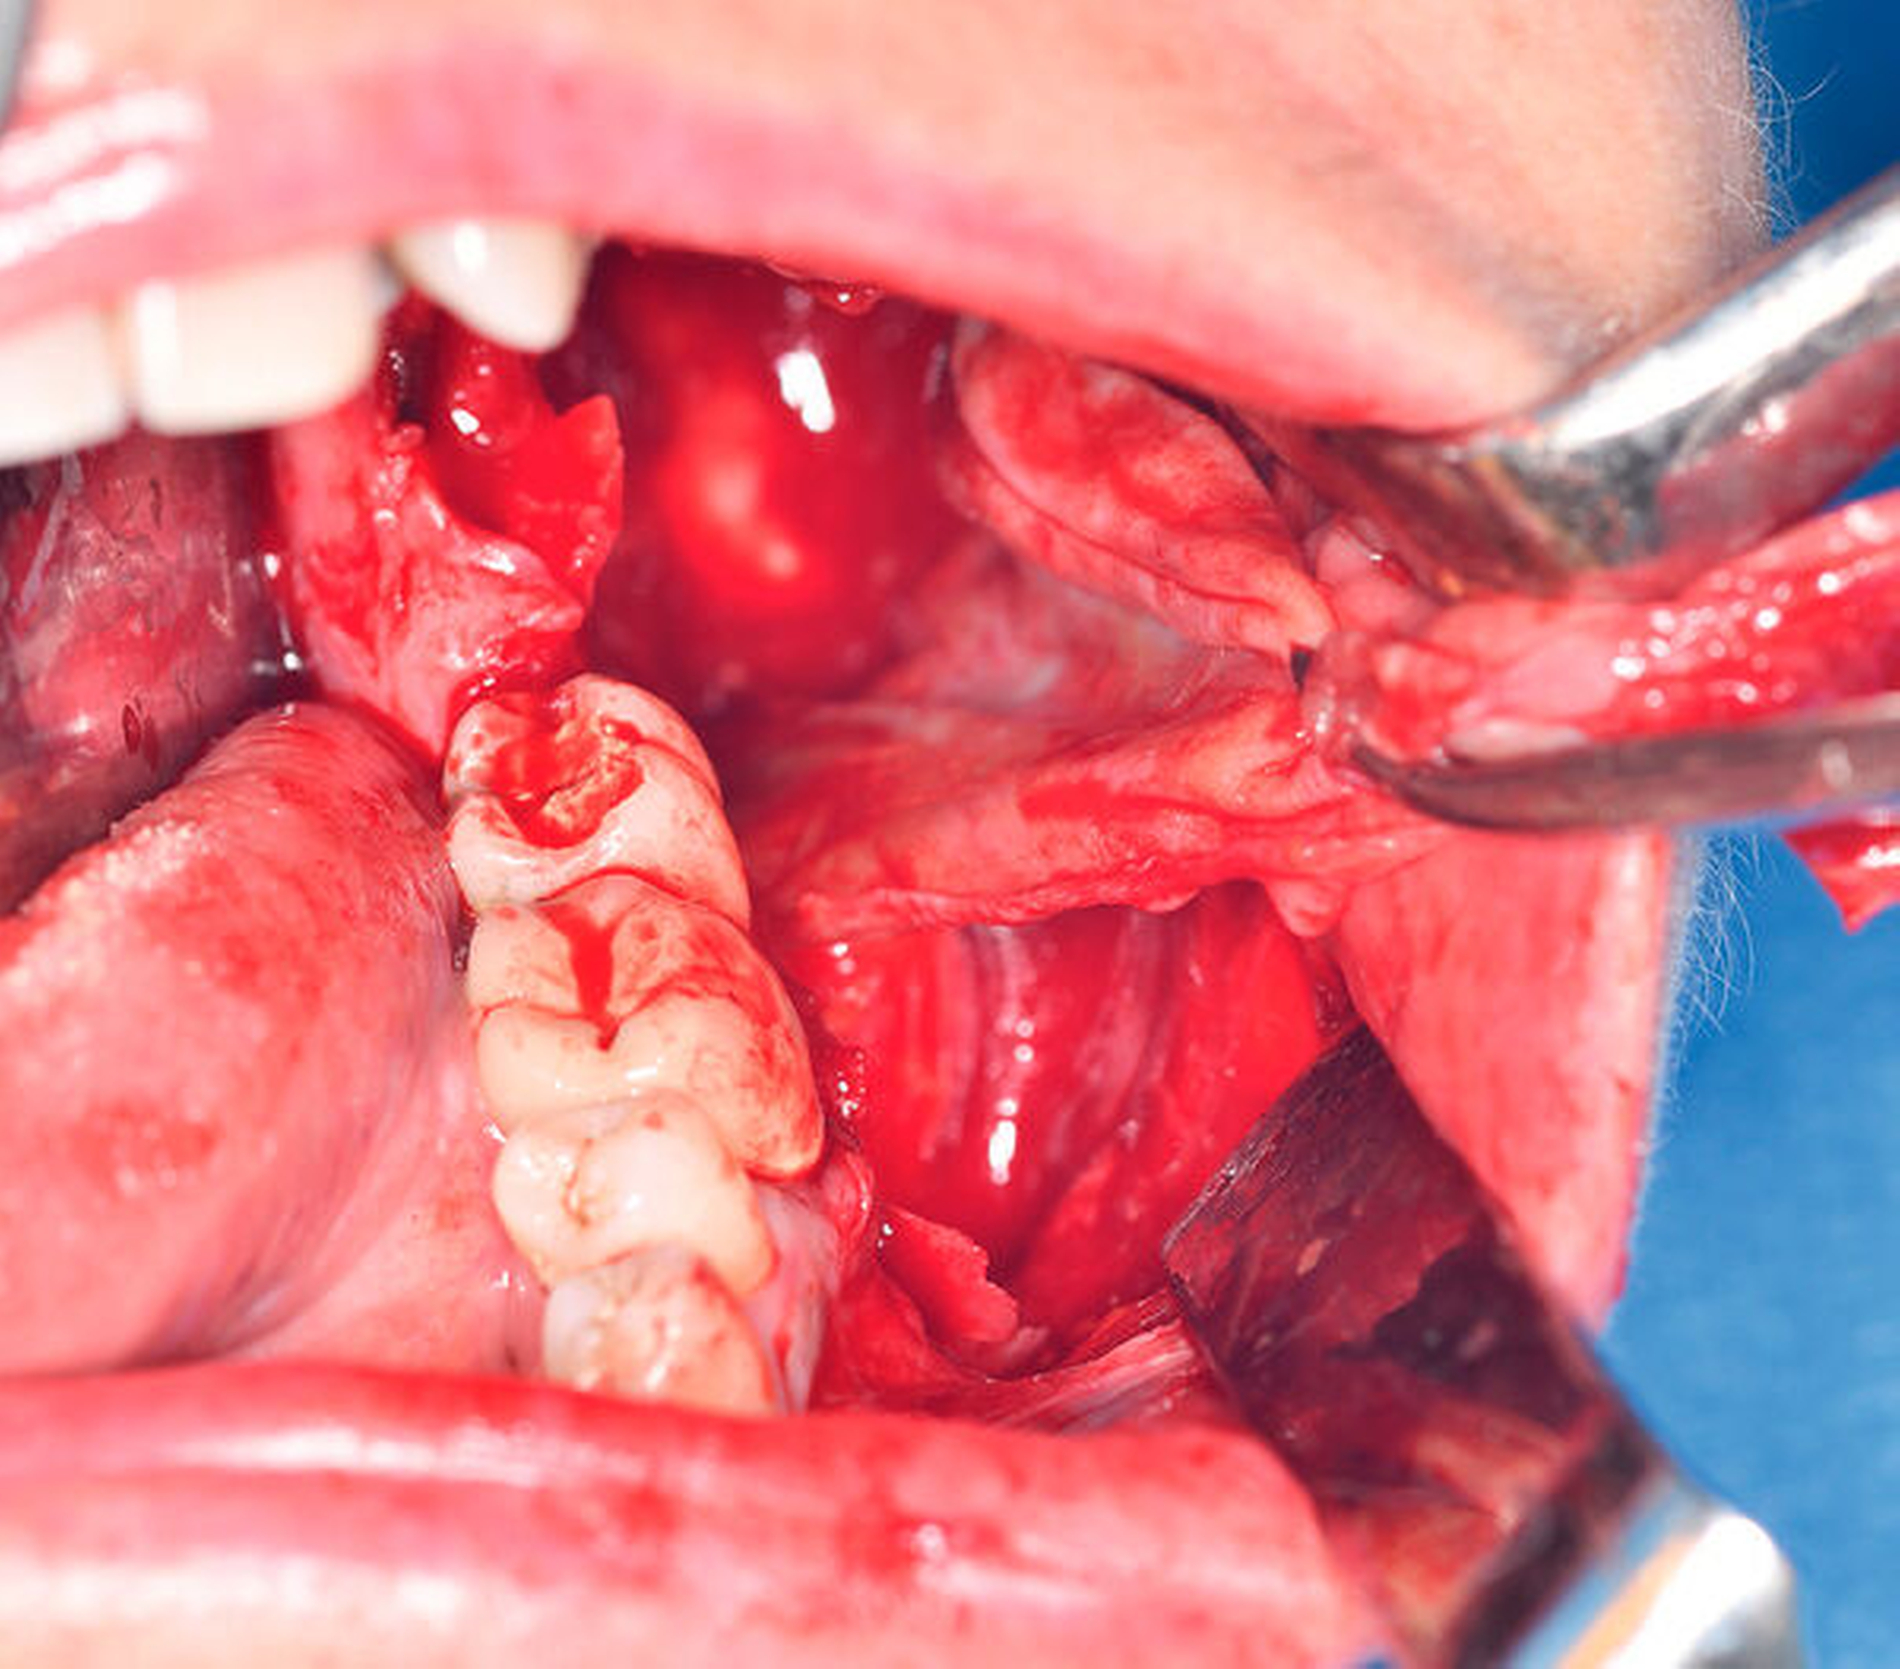

Aufgrund der erhöhten Frakturgefahr bei bereits ausgedehnter Knochenresorption wurde mit der Patientin nach Anfertigung der komplettierenden 3-D-Bildgebung (digitale Volumentomografie) ein zeitnaher Termin zur Diagnosesicherung durch Probeentnahme in Allgemeinanästhesie vereinbart (Abbildung 2). Bereits in der darauffolgenden Woche konnte der Eingriff durchgeführt und die intraoperativ gut erreichbare, klinisch als follikulär anmutende Zyste in toto im Sinne einer Zystektomie mit Osteotomie des Zahnes 38 entfernt werden. Hierbei stellten sich das Vestibulum als solide verstrichen und die darunterliegende Kortikalis nach Schleimhautpräparation pergamentartig ausgedünnt dar (Abbildung 3). Auf eine zusätzliche Stabilisierung mittels Osteosyntheseplatte wurde bei ausreichendem Restknochen verzichtet.

Während kleinere Zysten vornehmlich via Zystektomie und Extraktion des retinierten Zahns (bei im Durchbruch befindlichen Zähnen sollte eine isolierte Zystenbalgentfernung mit kieferorthopädischer Eruptionsunterstützung zum Zahnerhalt in Erwägung gezogen werden) behandelt werden, ist die Zystostomie zur primären Reduktion des knöchernen Zugangstraumas mit sekundärer Zystektomie nach histopathologischer Diagnosesicherung das Therapiekonzept der Wahl [Neville et al., 2016]. Da im vorliegenden Fall die vestibuläre Knochenlamelle bereits pergamentartig ausgedünnt war und sich der Zystenbalg problemlos in toto enukleieren ließ (Abbildungen 3a bis 3d), entschied man sich hier für eine primäre Zystektomie. Eine engmaschige andauernde Nachsorge ist nach histopathologischer Befundsicherung nicht zwingend erforderlich und kann im Rahmen der allgemeinen zahnärztlichen Routineuntersuchungen durchgeführt werden.